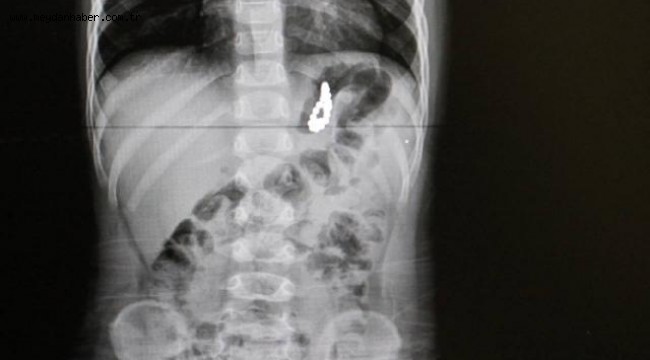

Pamukkale ilçesinde yaşayan Özdemir ailesinin 19 aylık çocukları Murat, geçen hafta aniden rahatsızlanınca özel bir hastaneye götürüldü. Akciğer enfeksiyonu şikayeti üzerine çekilen röntgende, çocuğun midesinde yabancı cisim bulunduğu tespit edildi.

Pamukkale Üniversitesi Hastanesine götürülen çocuk için burada acil ameliyat kararı alındı. Çocuk Gastroenteroloji Öğretim Üyesi Doç. Dr. Halil Kocamaz ve ekibi, Murat'ın midesindeki 5 milimetre çapındaki 17 boncuk mıknatısı yaklaşık 2 saat süren operasyonla çıkardı.

Midedeki boncuk şeklindeki mıknatısların bir arada toplanması, röntgen ve endoskopi görüntüsüne de yansıdı. Operasyonun ardından normal servise alınan Murat Özdemir'in tedavisi sürüyor.